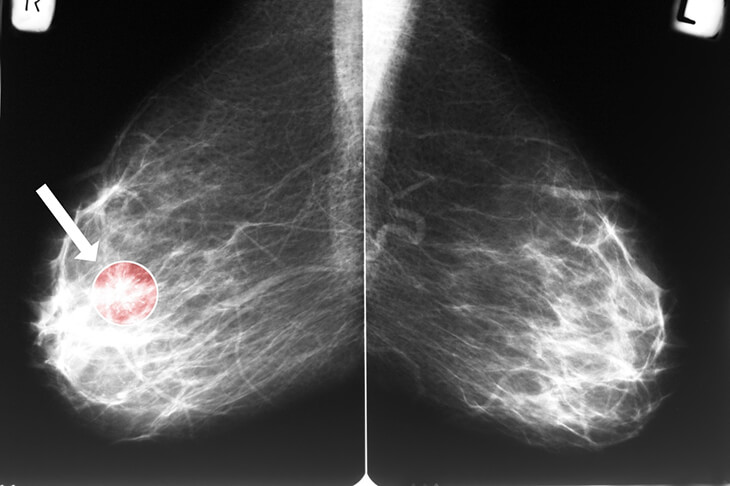

What’s best for your breast?

October is breast cancer awareness month. It’s a great time to go over a few common questions women have regarding breast health and breast cancer detection.

The first step in breast health is breast self-awareness, which means that you are aware of what is normal for your breast and can detect small changes. Self-detection results in almost one-half of all cases of breast cancer being found in women aged 50 years and older. A woman herself often finds breast cancer. In women younger than 50 years, more than 70% of breast cancer cases are self-detected.

Are there signs and symptoms related to breast cancer?

The most common symptom of breast cancer is a new lump or mass. A painless, hard mass with irregular edges is more likely to be cancer, but breast cancers can be tender, soft, or round. They can even be painful. For this reason, it’s essential to have any new breast mass, lump, or breast change checked by experienced healthcare professionals.

Should I have a clinical breast exam?

Yes! A healthcare provider should perform a clinical breast exam and can help find lumps that may need further testing and evaluation. The exam should be done every 1-3 years for women aged 25-39 and women aged 40 and older should have an exam every year.

When should I start having mammograms?

The American College of Obstetricians and Gynecology recommends that a woman of average risk start at age 40 and have mammograms every 1-2 years. For more information regarding mammograms, click on the link in the reference section below or speak to your healthcare provider.

Early detection of breast cancer is an essential factor in survival rates. Having yearly wellness exams is a great way to stay on top of your health. We would love to answer any questions you have regarding breast health or any part of your wellbeing.